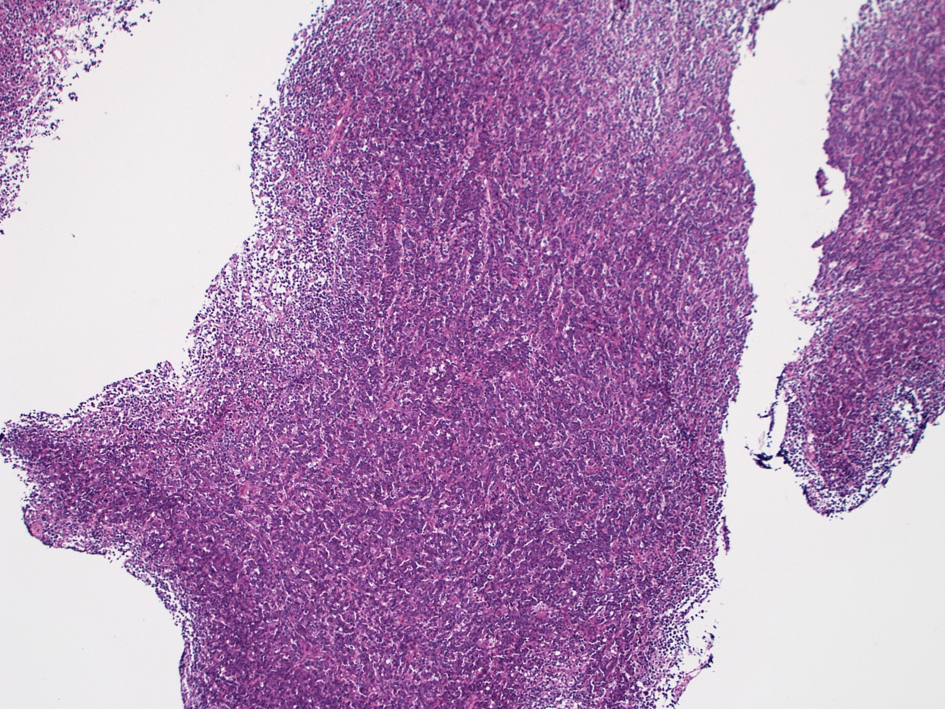

山梨大学医学部 Dr.大石直輝: 骨髄HEではvesicularな核をもつ大型異型細胞がorganoid pattern, 類上皮様配列をとり増殖している。癌腫の転移と紛らわしい所見。

腫瘍細胞は接着性がみられ, 索状に増殖, 上皮性腫瘍のように見える。

ALK+ LBCLは形態的にリンパ腫に見えないことがある。(CKが染まる場合, 低分化な癌に誤診されてしまう)

ALK+ LBCLは形質細胞腫に見えることがある。